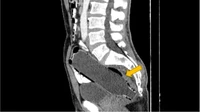

Tahun 2022, seorang pria berusia 50 di Iran tahun mencoba memasukkan botol berukuran 250 cc air ke dalam anusnya. Setelah 3 hari, ia mengalami gejala anoreksia, nyeri perut, dan tidak bisa buang air besar. (Foto: Clinical Case Reports)